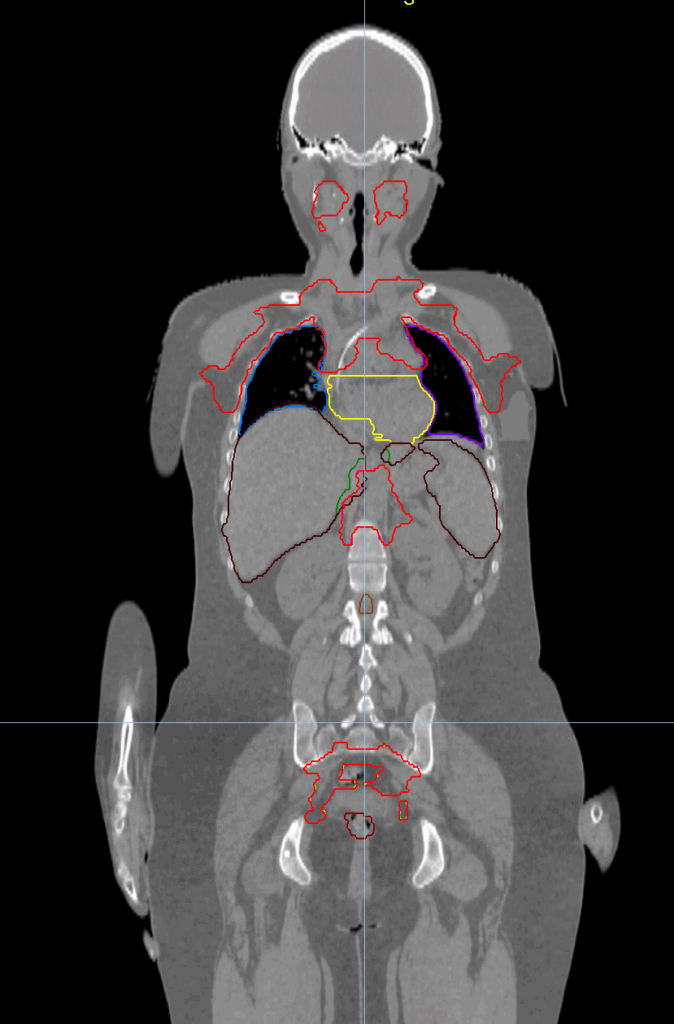

Planning CT Images